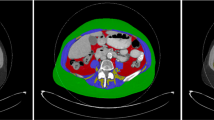

Patients (n = 3) whose CT quality was not suitable for analysis on ImageJ software due to artifact or a restricted field of view for waist circumference or skeletal muscle mass measurement were excluded. The measurement technique is detailed in a previously published article by Gomez et al. [11] and summarized in Fig. 1.

Measurement technique summarized in three steps. Step 1: after adjusting the image threshold between − 250 and + 1000, we click on the outer surface of the threshold-highlighted area with a wand tracing tool which delineates the abdominal perimeter (yellow contour in 1a). Step 2: the image returns to its original gray color after adjusting the threshold between − 250 and − 250 and we remove the yellow line by clicking on freehands selection tool. A stylus is then used to trace the outer muscle perimeter (arrow in 1b and 1c) for which measurement is obtained after making the threshold between − 29 and + 150. Step 3: the threshold is adjusted back between − 250 and − 250 then tracing of the inner muscle perimeter (arrowhead in 1c) is performed using the stylus. This measurement is also obtained after adjusting the threshold between − 29 and + 150

16-year-old girl with no past medical history presenting with 5-day history of right lower quadrant abdominal pain and nausea. She had abdominal and pelvic ultrasound exams which showed no appendicitis or pelvic pathology. She was admitted for pain control and serial abdominal exams. A CT scan of abdomen and pelvis was obtained due to persistent abdominal pain and showed no acute pathologies. The patient was discharged home after 24 h with clinical improvement. No ICU admission or mechanical ventilation was needed during her short hospital stay. Her BMI was 25.64 (obese for age and sex). Waist circumference measures 86.5 cm (yellow contour in 1a) and skeletal muscle mass measures 4.5 cm2 (arrow and arrowhead for outer and inner muscle perimeter and area, respectively, in 1b)